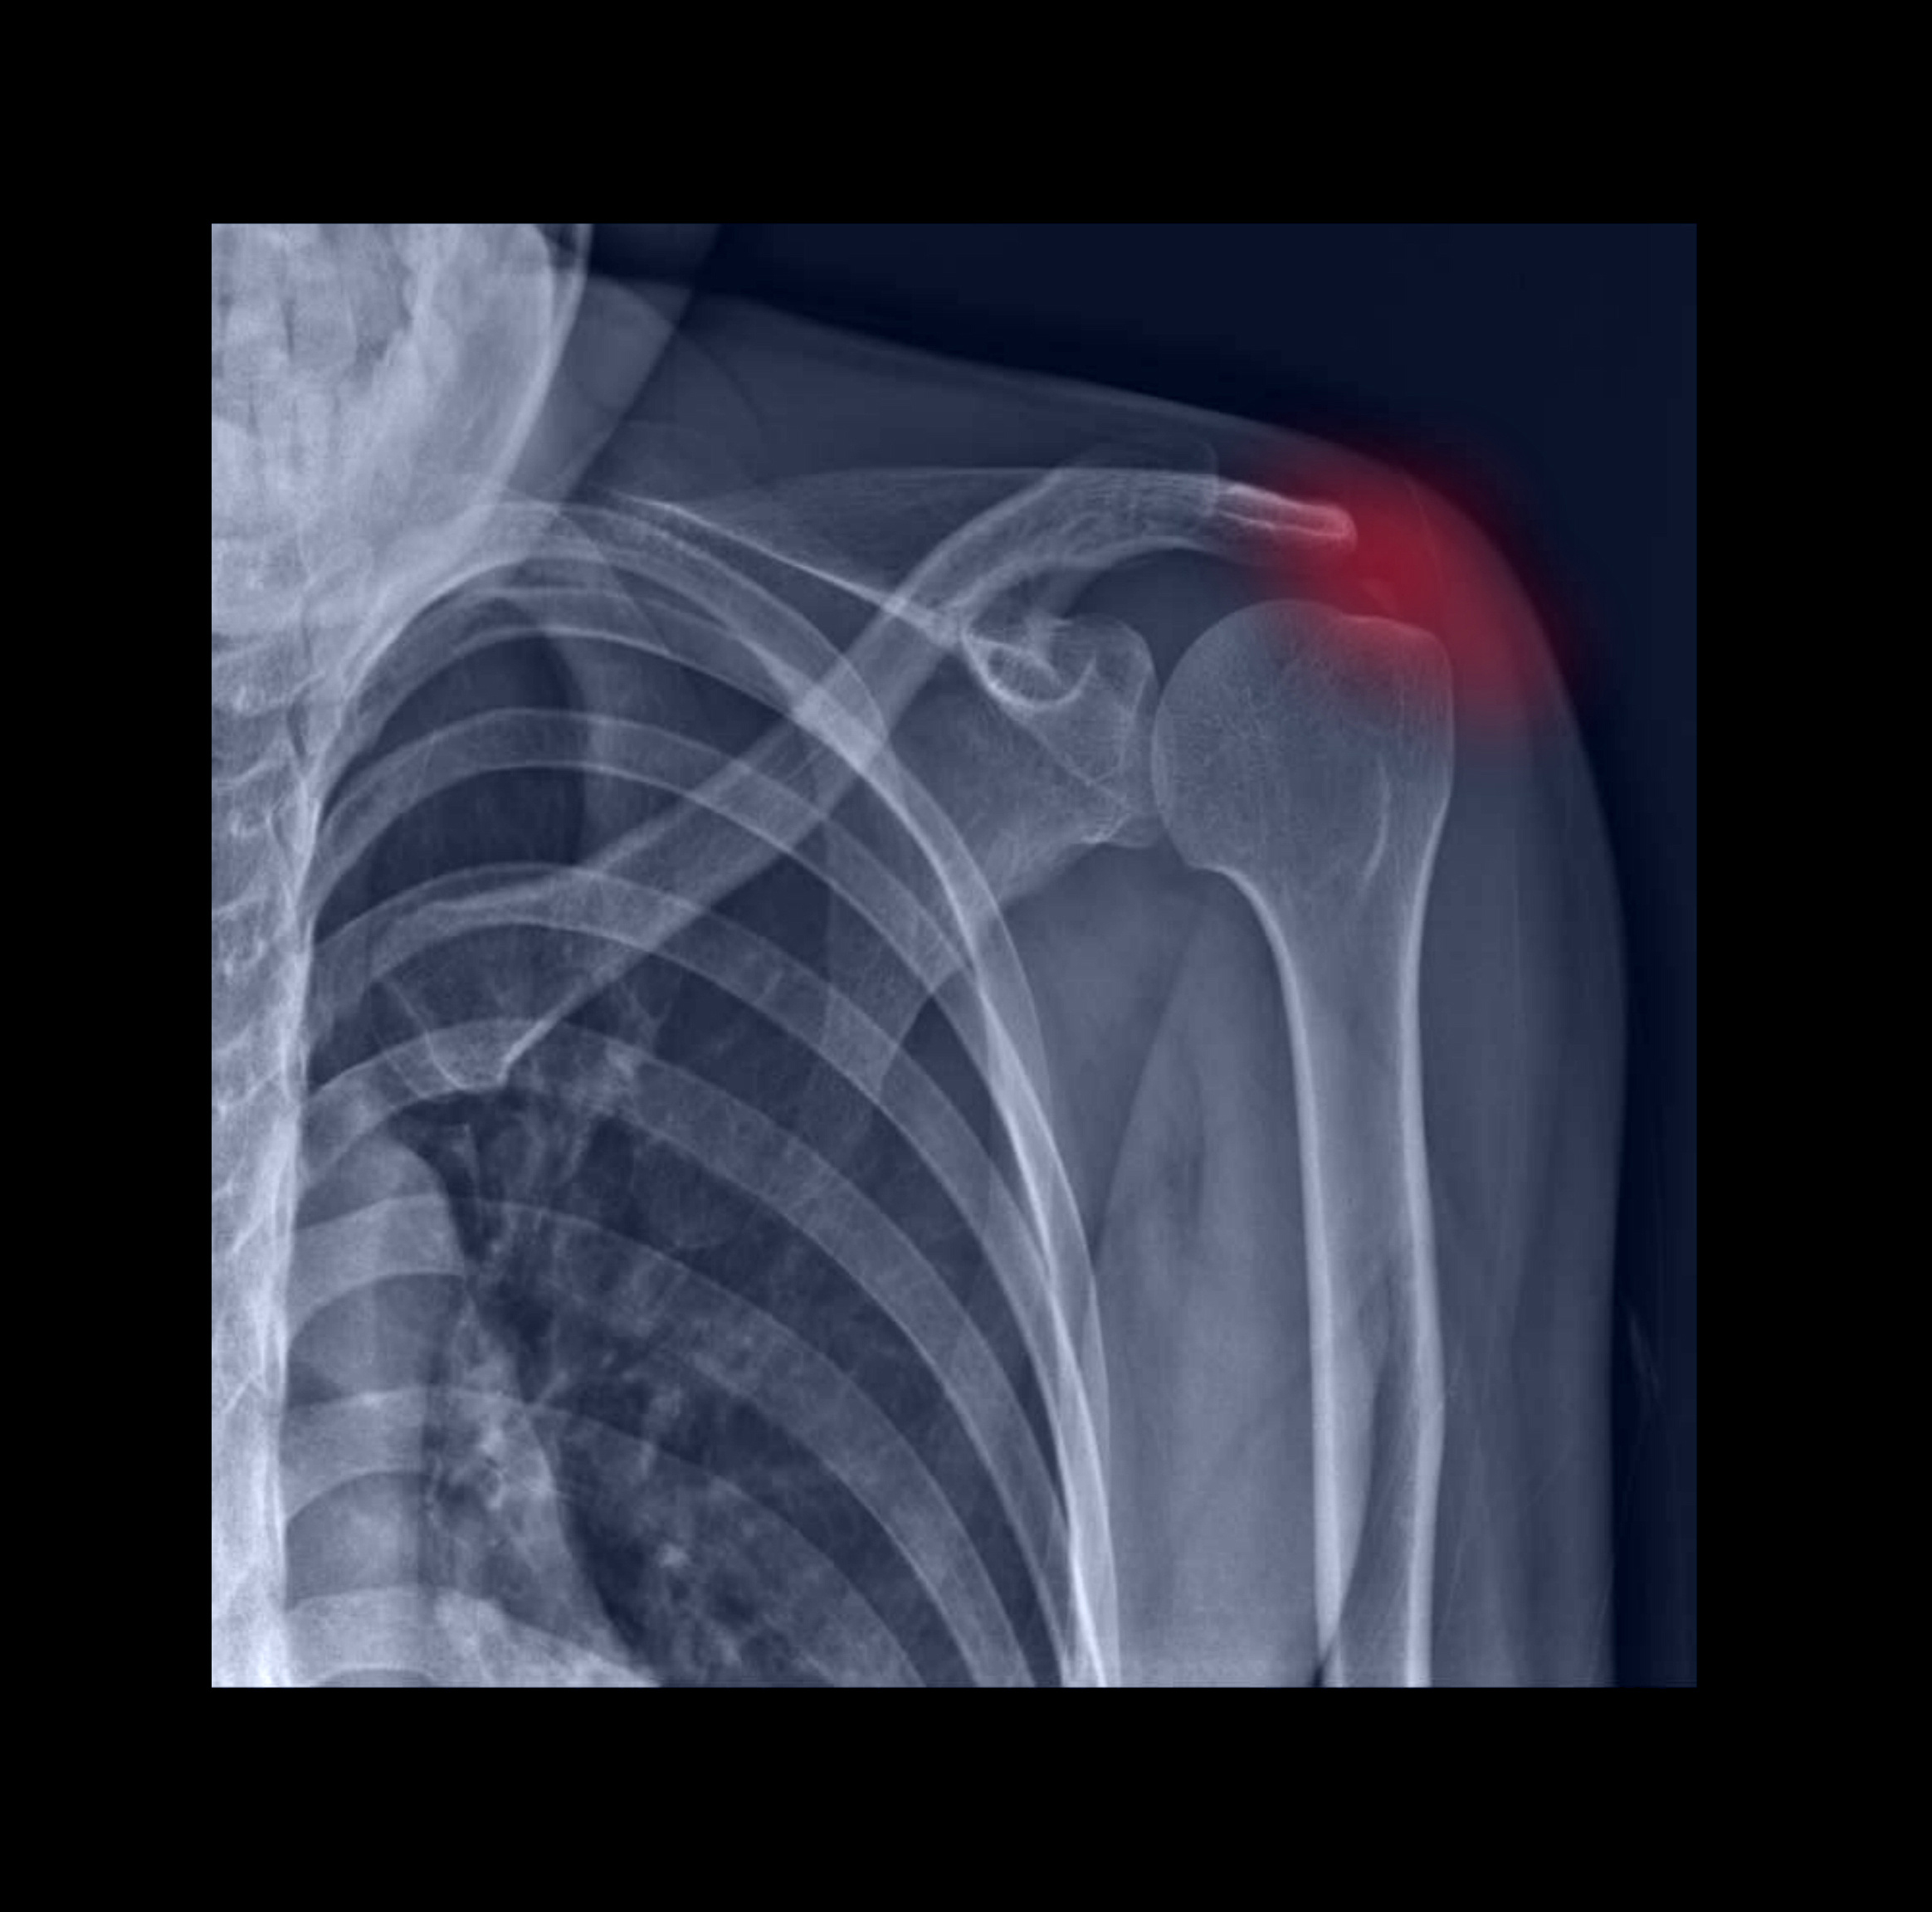

Impingement Syndrom

Bei der häufigsten schmerzhaften Funktionsstörung der Schulter, dem Schulter Engpass Syndrom oder Impingement Syndrom, kommt es durch Reiben und Einklemmen des inneren Sehnenmantels und des darüber liegenden Schleimbeutels am Schulterdach zur einer Entzündung des Schleimbeutels und bei längerem Verlauf auch des Sehnenmantels.